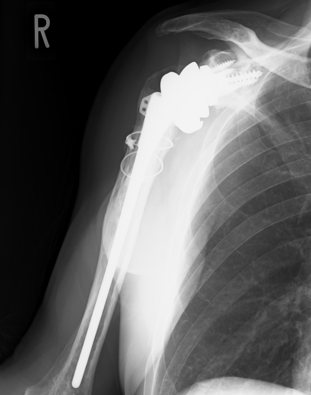

別の方ですが

この方は同種骨を使用していません。割れ目の大きさで同種骨は使用しなくても十分上腕骨の割れ目はふさがります。